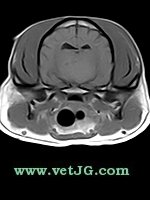

RESONANCIA MAGNÉTICA

AXIAL